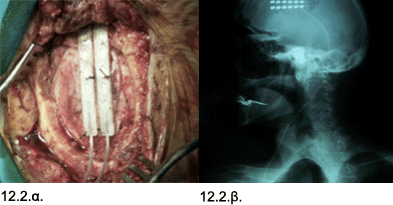

Εικόνες 12.2.α. & 12.2.β. Διεγχειρητική φωτογραφία που απεικονίζει την τοποθέτηση δύο ηλεκτροδίων (12.2.α.), και ακτινογραφία κεφαλής που απεικονίζει την θέση των δύο ηλεκτροδίων (12.2.β.).

Ιστορικό: Ο ασθενής 77 ετών, έπασχε από προσωπαλγία με χαρακτηριστικά «άτυπης νευραλγίας τριδύμου» αριστερά κατά τα τελευταία 7 έτη. Είχε υποβληθεί σε φαρμακευτική αγωγή με σχεδόν το σύνολο των ενδεικνυομένων φαρμάκων σε συνδυασμούς, χωρίς ουσιαστική ύφεση του άλγους. Ο ασθενής λόγω της έντασης του πόνου είχε περιέλθει σε τραγική κατάσταση. Μετά τον έλεγχο με μαγνητική τομογραφία, ο ασθενής υποβλήθηκε σε ελάχιστα επεμβατική τοποθέτηση επισκληριδίων ηλεκτροδίων στην κεφαλή, στην περιοχή που αντιπροσωπεύεται ή αριστερή πλευρά του προσώπου, στον δεξιό εγκεφαλικό φλοιό. Η επέμβαση έγινε, μέσω πολύ μικρής κρανιοτομίας και μέσα σε ολίγες ημέρες, ο ασθενής παρουσίασε σημαντική βελτίωση του πόνου. Η βελτίωση έχει παραμείνει, ο ασθενής έπαψε έκτοτε να λαμβάνει αναλγητικά φάρμακα.